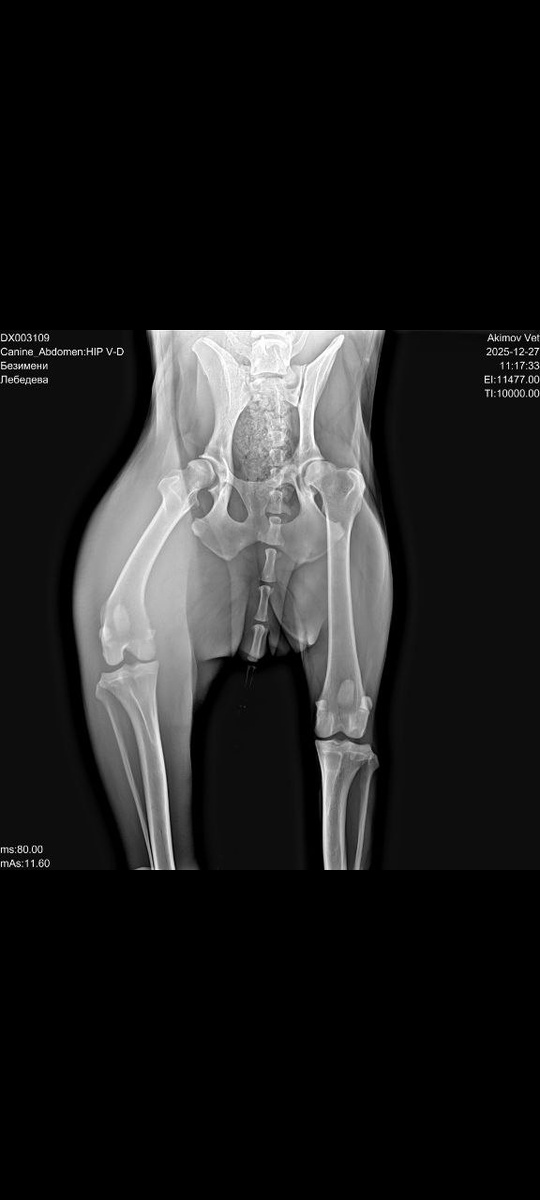

Ханну осмотрел ортопед.

По результатам рентгена и осмотра был поставлен диагноз:

полный разрыв крестообразной связки.

Как будто этого мало, на рентгене в брюшной полости обнаружили пулю.

След прошлой жизни, в которой у Ханны не было ни защиты, ни заботы.